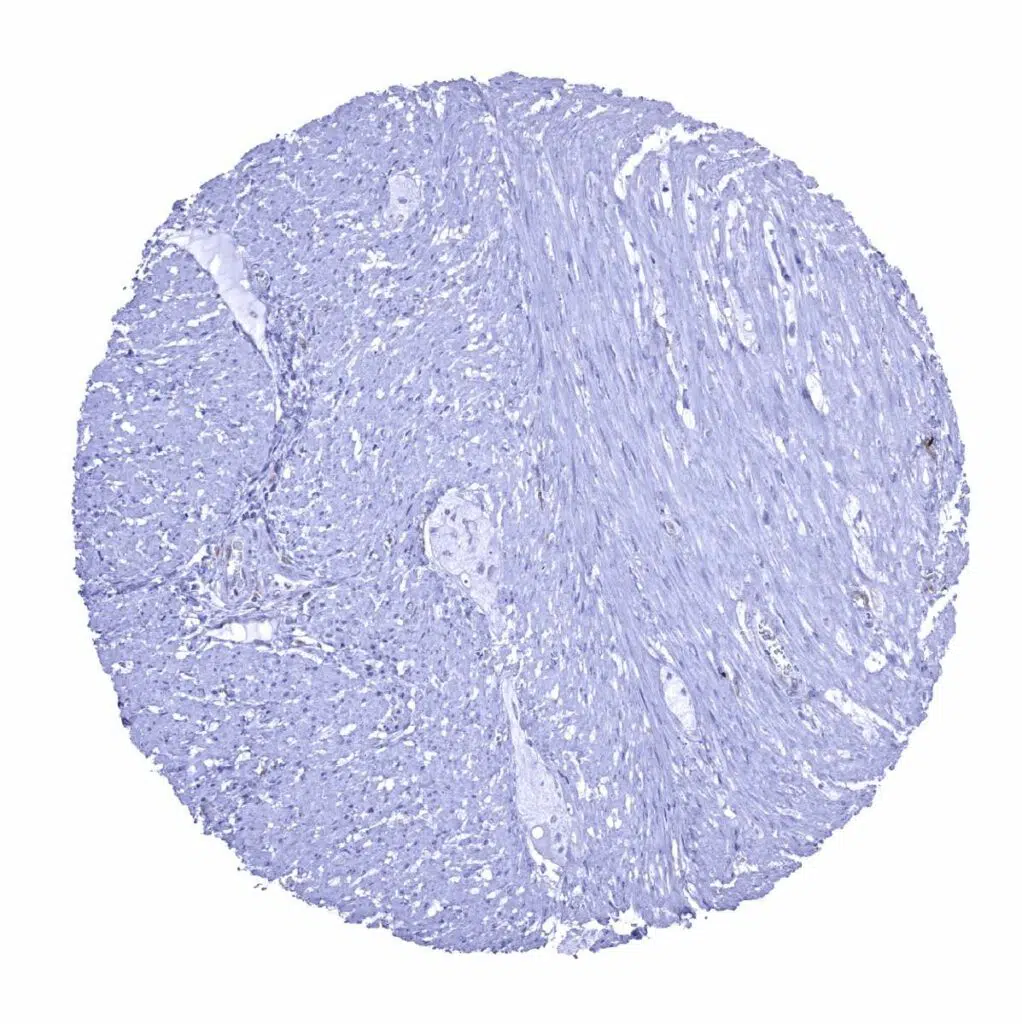

Urinary bladder, muscular wall

Uterus, myometrium – A weak GS staining is seen in few endothelial cells of small capillaries